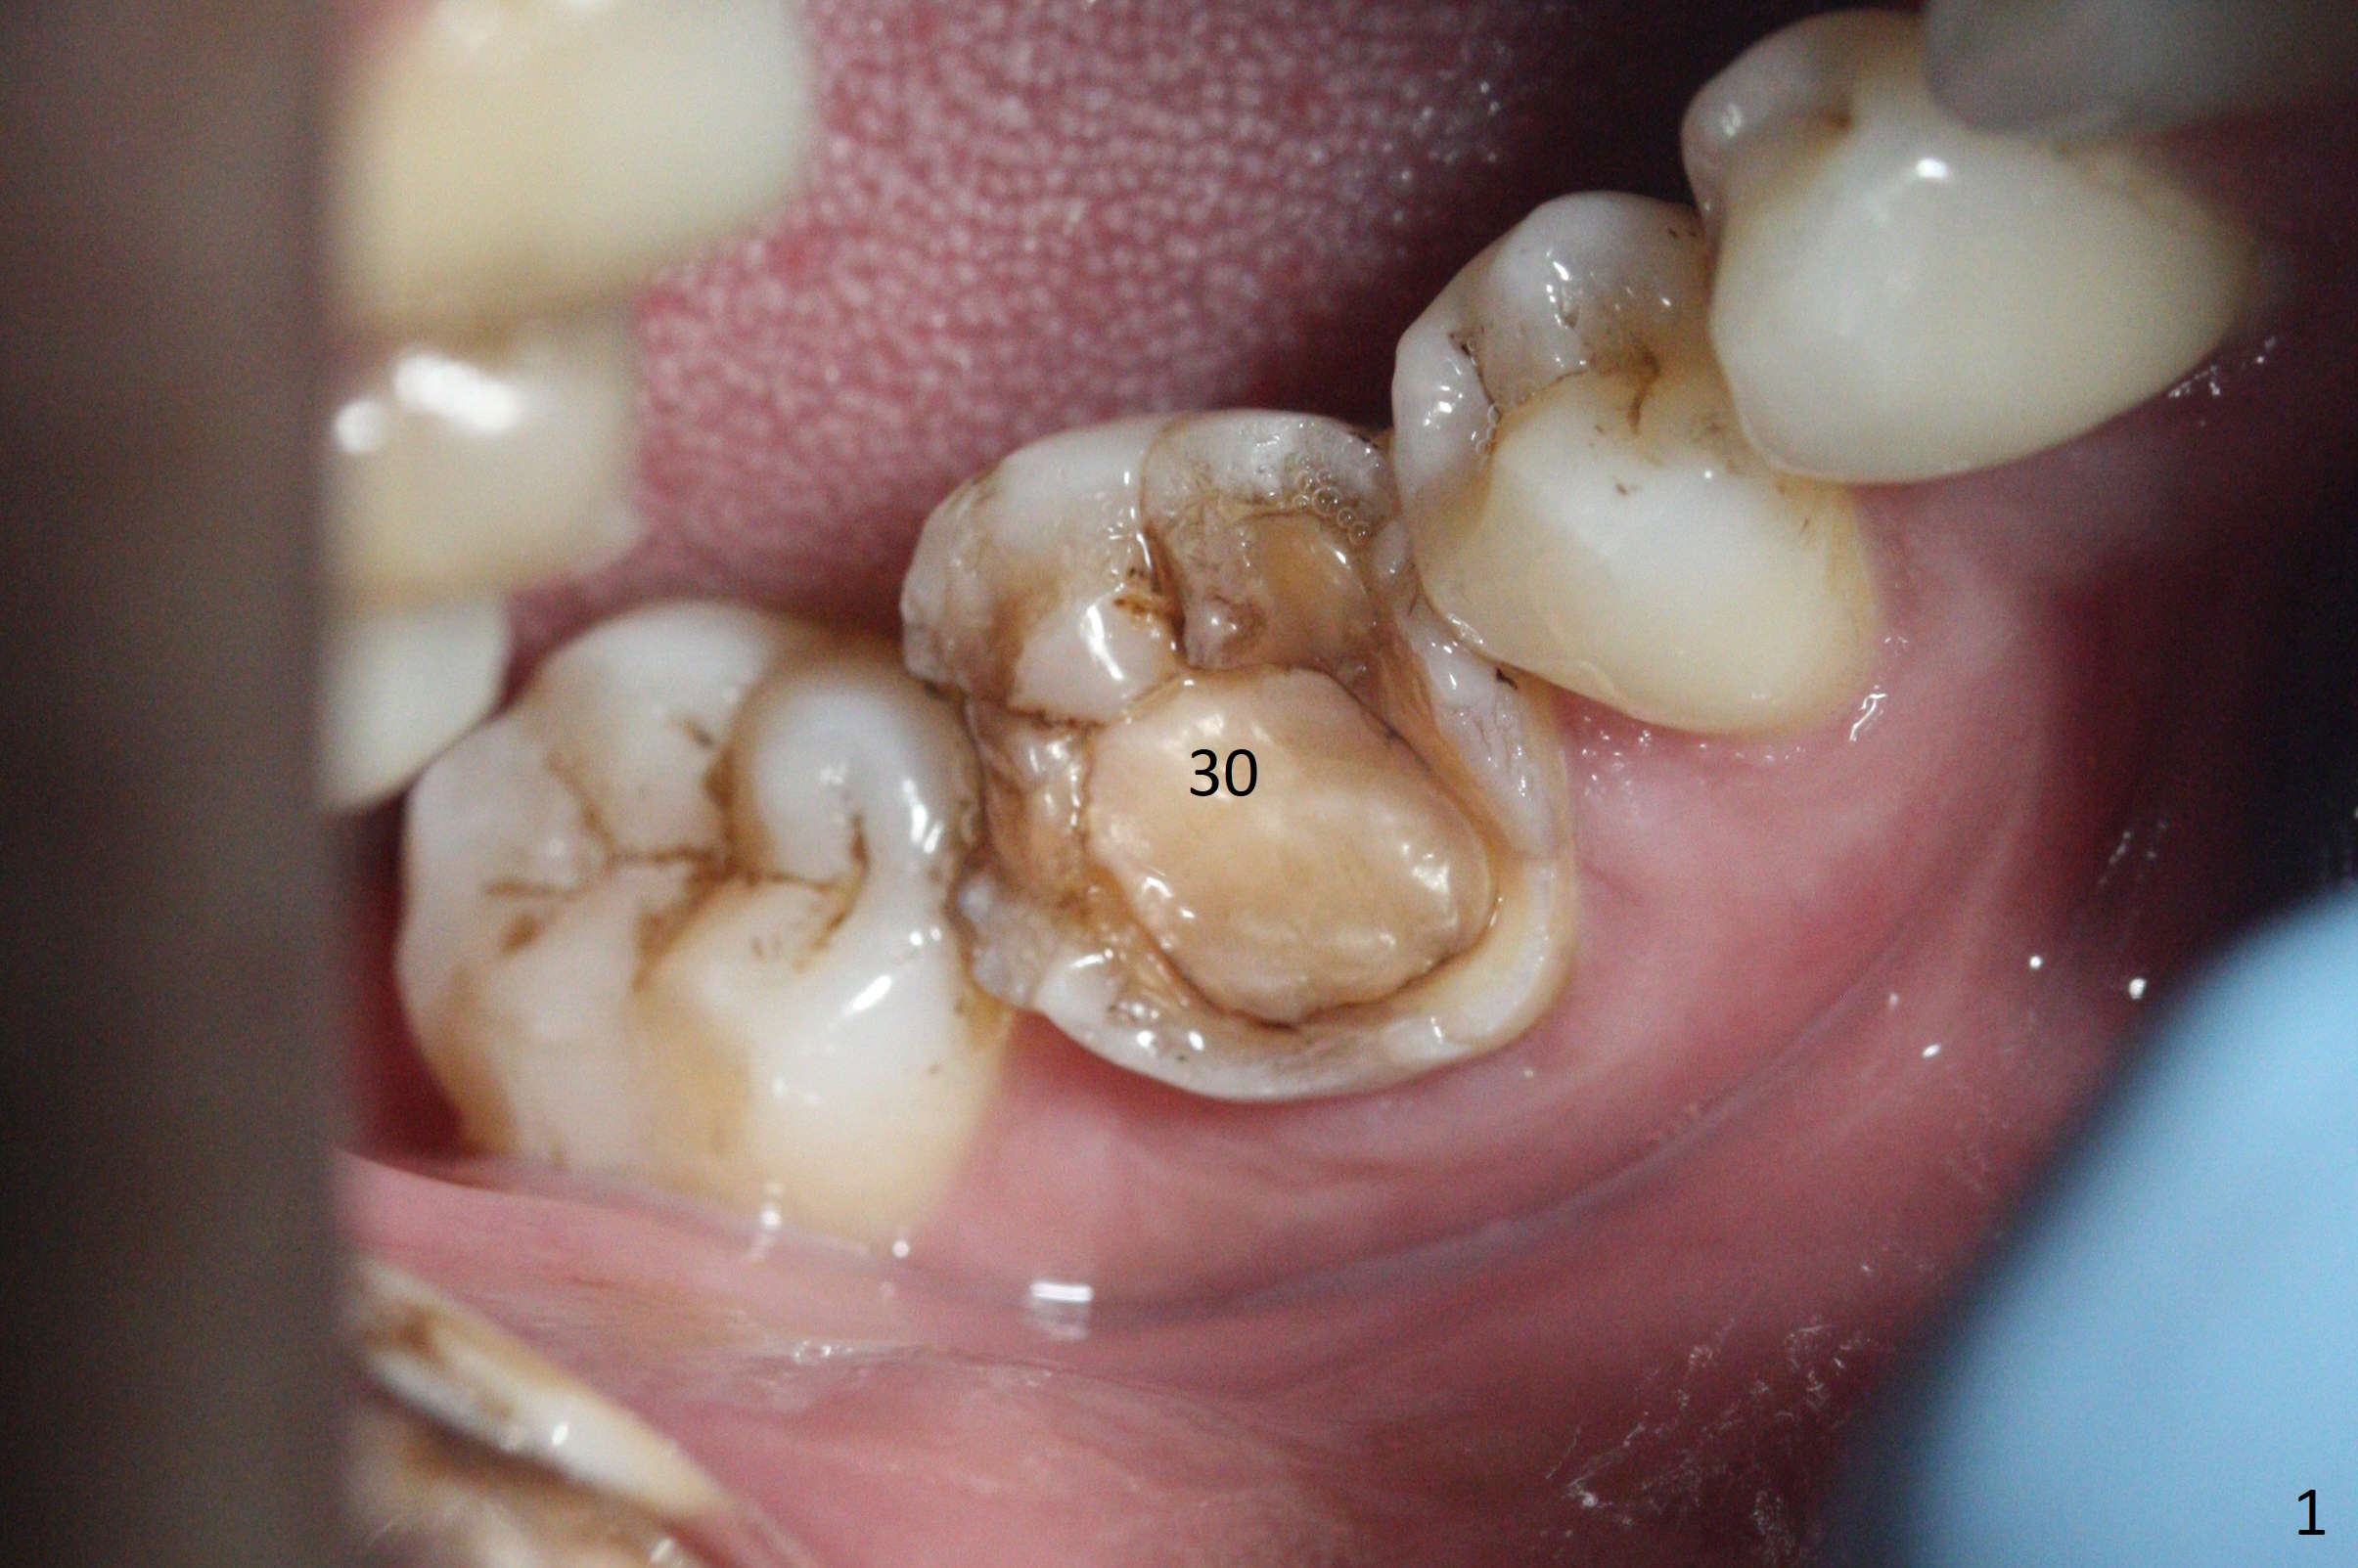

A 34-year-old man has a mobile molar post RCT (Fig.1,3) with lingual gingival recession (Fig.2). Possible bone defect is about 9 mm (Fig.3: purple line). There is approximately 7 mm native bone for primary stability (yellow line). Possible length of the implant to be placed will be 16 mm (9+7). Since the lingual gingiva is recessive (Fig.2), the osteotomy will be initiated more or less in the center of the socket bottom.